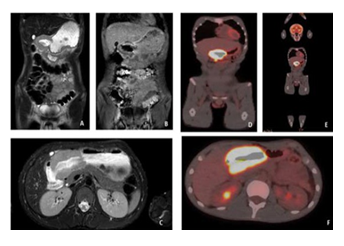

The patient referred to the Pediatric Hematology and Oncology Department for complete work-up and staging. Magnetic resonance imaging (MRI) examination Axial T2w and coronal T1w with gadolinium images demonstrated diffuse thickening of the gastric wall at the level of the pylorus (Figure 3 A,B,C). The positron emission tomography- computed tomography (PET-CT) scan Axial and coronal whole - body PET-CT fusion images (Figure 3 D,E,F) as part of the staging process revealed a hypermetabolic mass in the pyloric antrum with an SUV max of 21,6. There was

Figure 3: Magnetic resonance imaging (MRI) examination A and B: Axial T2w and C: coronal T1w with gadolinium images demonstrated diffuse thickening of the gastric wall at the level of the pylorus. The positron emission tomography-computed tomography (PET-CT) scan D and E: Axial and F: coronal whole - body PET-CT fusion images as part of the staging process revealed a hypermetabolic mass in the pyloric antrum with an SUV max of 21,6. There was also an enlarged hypermetabolic lymph node on the inferior surface of the hypermetabolic lesion. There were no other hypermetabolic findings.

also an enlarged hypermetabolic lymph node on the inferior surface of the hypermetabolic lesion. There were no other hypermetabolic findings.